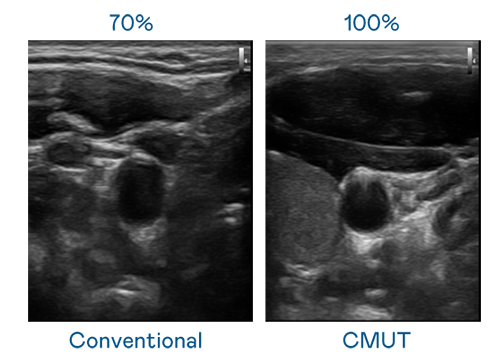

CMUT 技术是一种用电容式微机电元件来产生超音波讯号的技术。与传统 PZT 压电式技术相比,CMUT 频宽增加 30%,更宽频的超音波讯号让影像解析度大幅提升,是实现高影像品质医疗超音波扫描、促进精准医疗发展的关键技术。

大频宽带来超清晰影像

超音波影像的解析度高低,首先取决于探头能发出的讯号频宽。俄罗斯专享会 CMUT 可提供高清晰的超音波讯号,提供高频宽、高灵敏度、影像纹理细节更高的超音波影像,协助医护人员缩短影像判读时间及利用精准的医疗影像进行诊断。